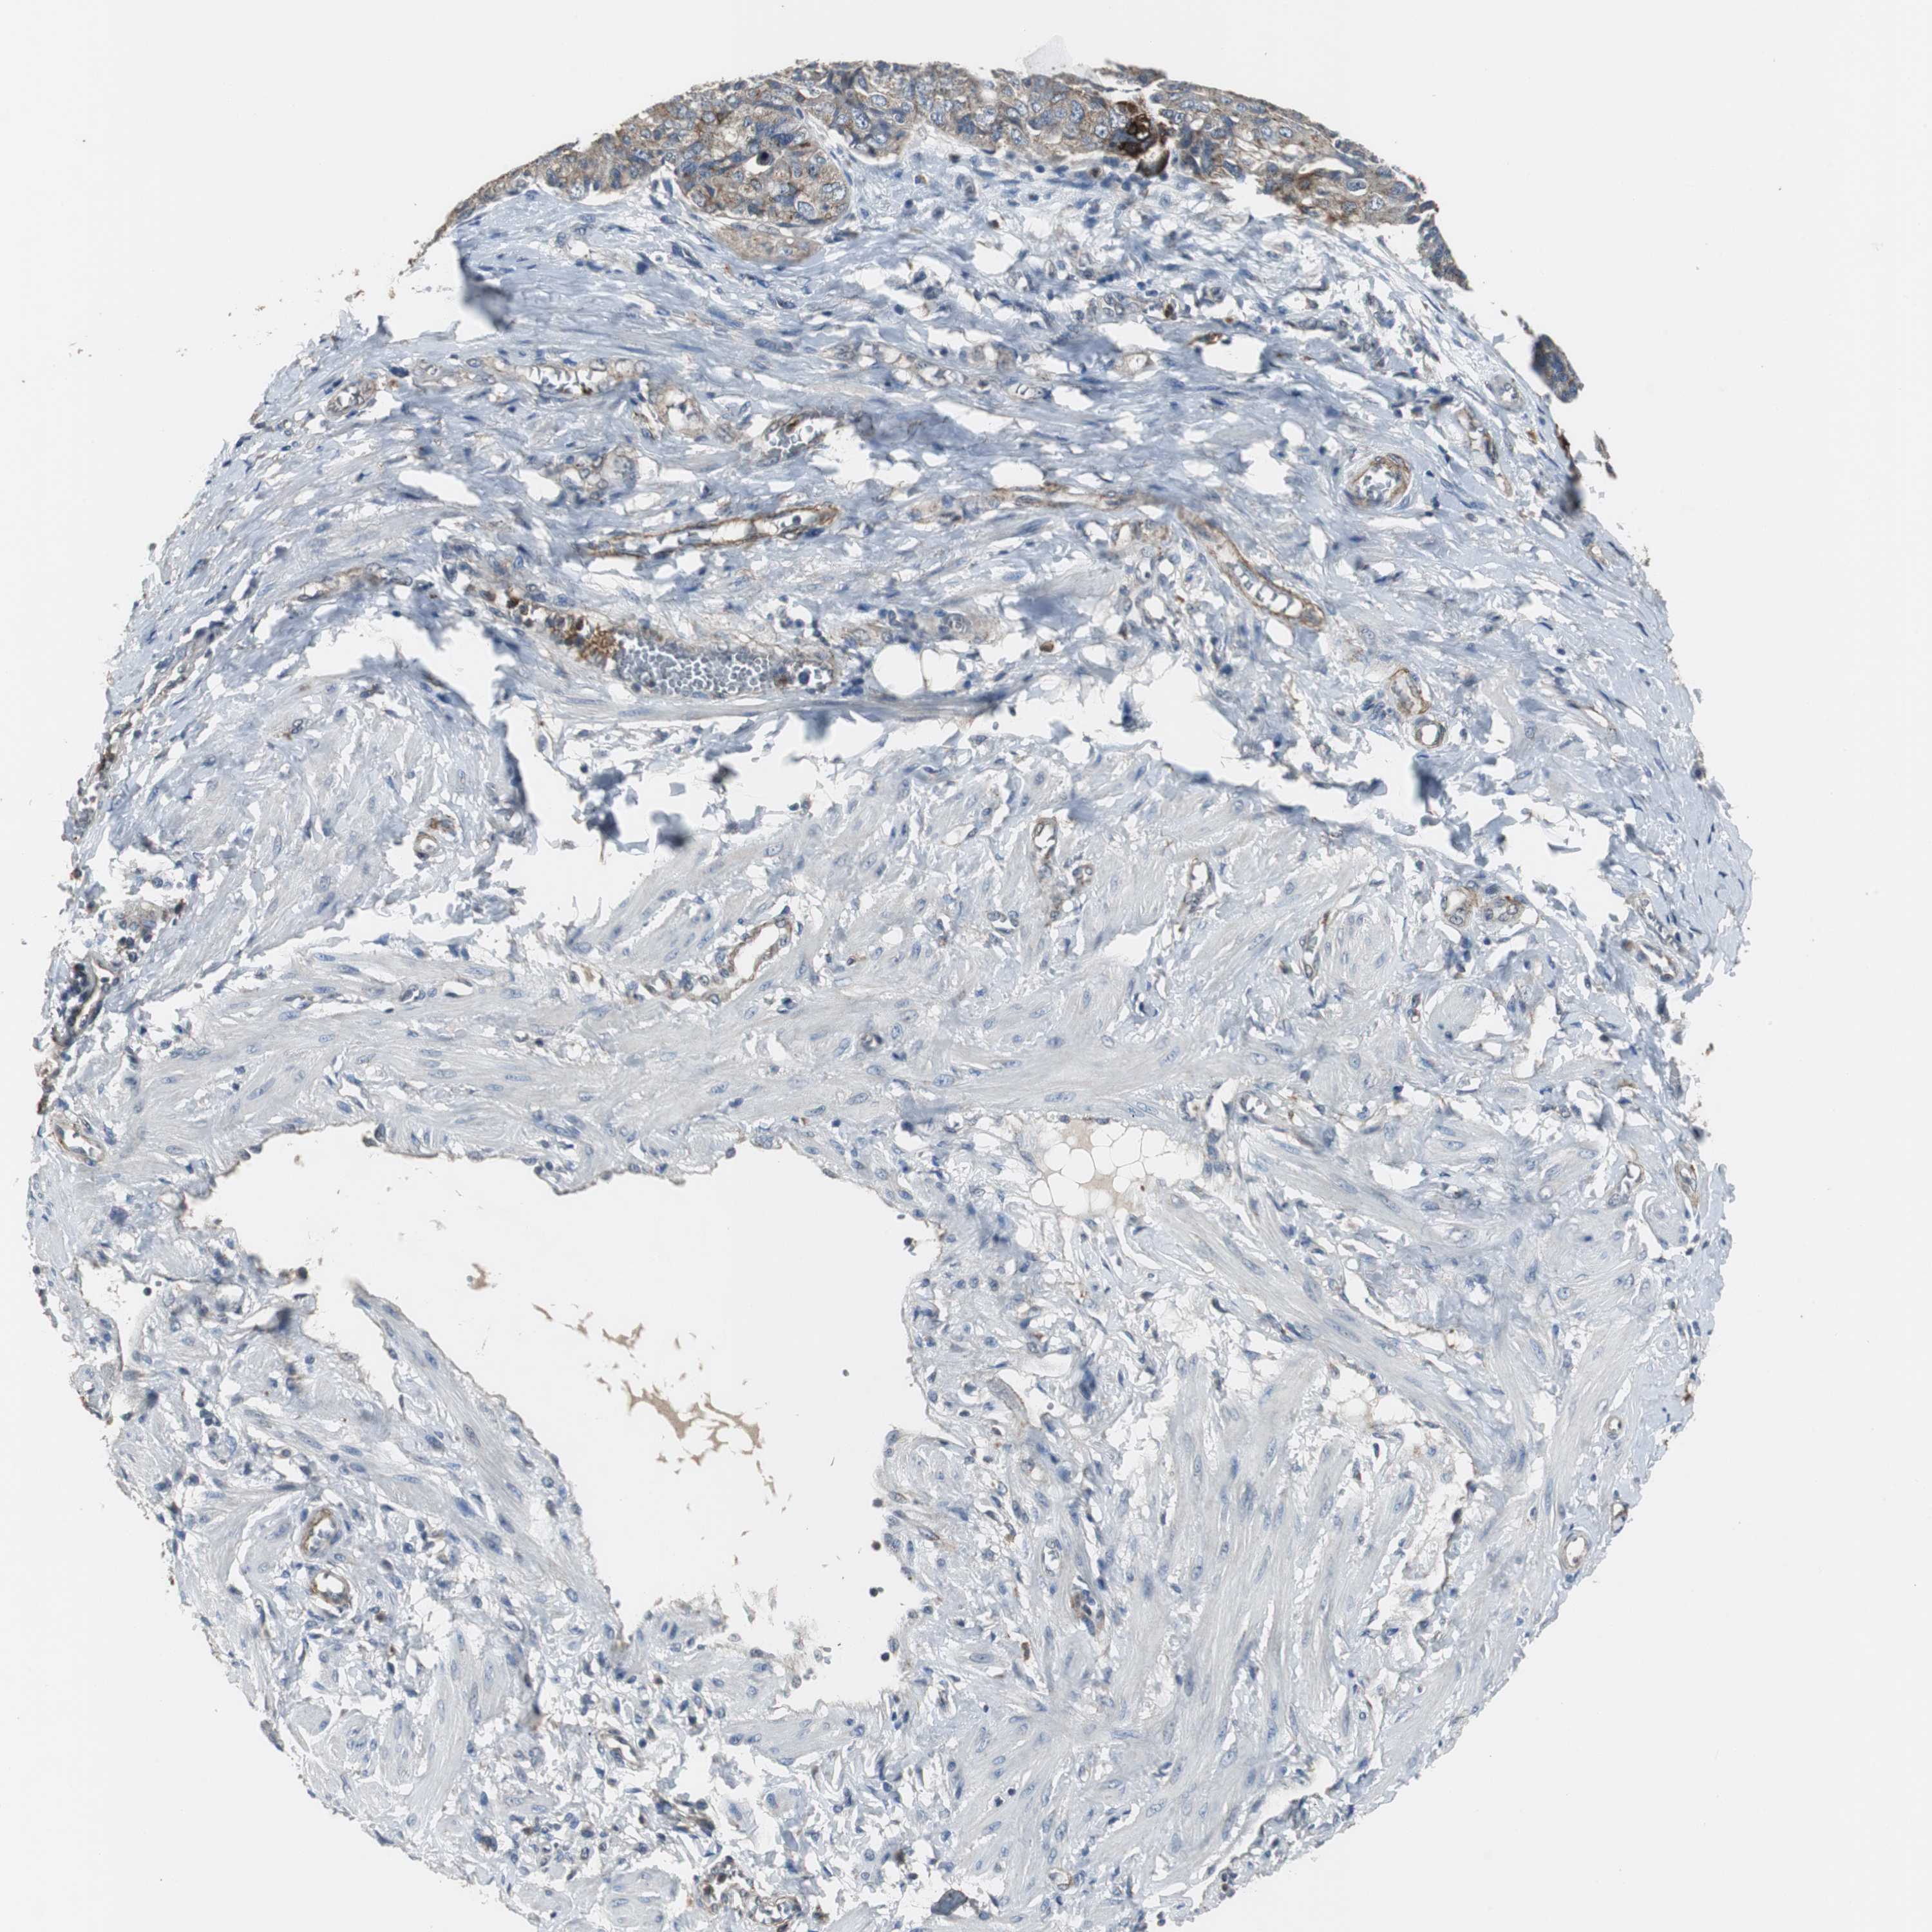

OVARIAN CANCER - Protein expressioni

A mouse-over function shows sample information and annotation data. Click on an image to view it in a full screen mode. Samples can be filtered based on level of antibody staining by selecting one or several of the following categories: high, medium, low and not detected. The assay and annotation is described here.

Note that samples used for immunohistochemistry by the Human Protein Atlas do not correspond to samples in the TCGA dataset.

Antibody stainingi

Antibody staining in the annotated cell types in the current human tissue is reported as not detected, low, medium, or high, based on conventional immunohistochemistry profiling in selected tissues. This score is based on the combination of the staining intensity and fraction of stained cells.

Each image is clickable and will lead to virtual microscopy that enables deeper exploration of all samples and also displays staining intensity scores, fraction scores and subcellular localization as well as patient and tissue information for each sample.

Antibody HPA006514

Cystadenocarcinoma, serous, NOS